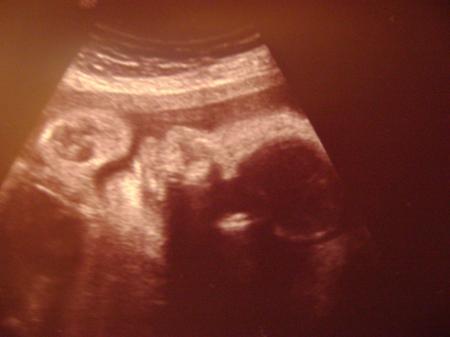

größer Waren heute beim Arzt und alles supi.... 31+1 1500g CTG in Ordnung- schöne Übungswehen drauf am Diabetes wieder vorbeigeschrammt (das heißt- Lebkuchen ohne schlechtes Gewissen) hab jetzt insgesamt knapp 12kg zugelegt -also bis auf nen klitzekleinen Pilz alles wunderbar.Kann gar nicht glauben das es nur noch 9-10 Wochen sind...uhhhh,wenn ich an die Geburt denke wird mir doch etwas mulmig Ich hänge mal ein Bild von meinem Flo und Bauch an

Bild zu ~~~EMIL- wird immer ... - Forum für Februar - Mamis